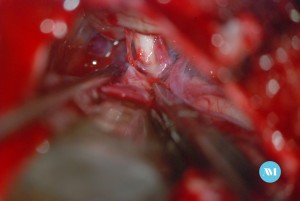

Algunos pacientes pueden requerir cirugía para aliviar la presión sobre el nervio. Las técnicas:

- Cirugía para extirpar un vaso sanguíneo que está ejerciendo presión sobre el nervio trigémino (llamada descompresión microvascular o DMV).